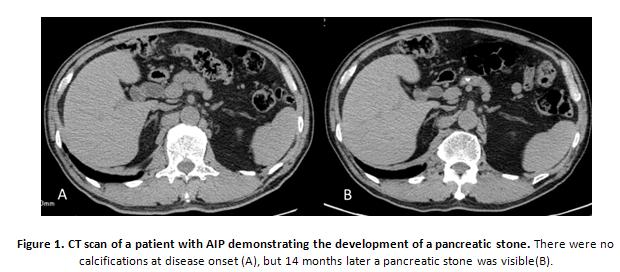

Most patients with type 1 AIP (referred to as “AIP” in this section) respond favorably to corticosteroid therapy, which results in the amelioration of symptomatic, radiographic, serologic, and pathologic findings. It is possible for patients to have a spontaneous recovery. However, during long-term follow-up, some patients with AIP are noted to progress to the advanced stage of pancreatic stone formation after recurrence, which may be similar to the findings of chronic pancreatitis (Figure 1) (29, 30, 40). In addition, the possibility of an association with malignant conditions, such as pancreatic cancer or other malignancies has been reported (4, 5, 10, 32, 37, 44).

AIP is characterized by high serum IgG4 concentration,IgG4-positive staining plasma cell infiltration in affected pancreatic tissue, and a favorable response to corticosteroid therapy. Imaging analyses by ultrasonography (US), computed tomography (CT), and endoscopic retrograde cholangiopancreatography (ERCP) show sonolucent (i.e., hypoechoic) swelling and irregular narrowing of the main pancreatic duct, both of which are due to lymphoplasmacytic inflammation at the acute stage. In 1995, Yoshida et al. first proposed the concept of AIP, which was considered to be free from calcification and to rarely progress to ordinary chronic pancreatitis (46). Although most patients have a favorable response to corticosteroid therapy, some develop pancreatic atrophy and stone formation with irregular dilatation of the main pancreatic duct (MPD) (30, 40). These imaging findings mimic those of chronic pancreatitis, suggesting that in some cases AIP may progress into chronic pancreatitis.